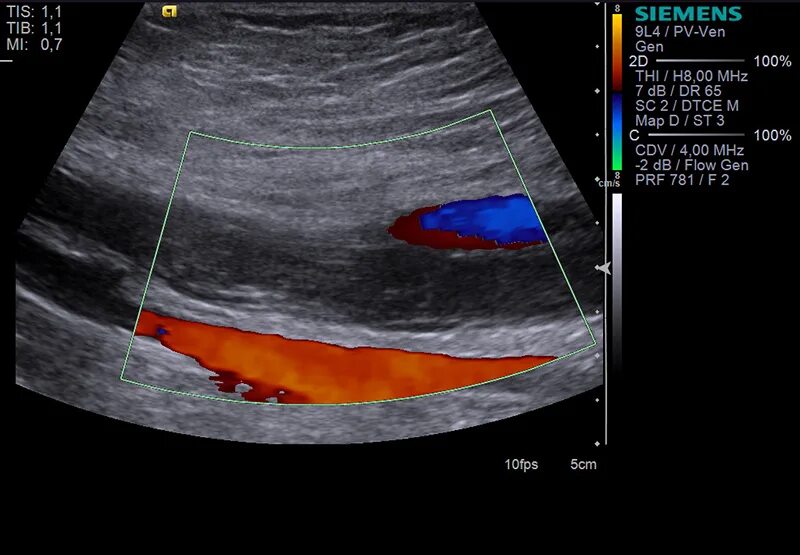

Атеросклероз на узи